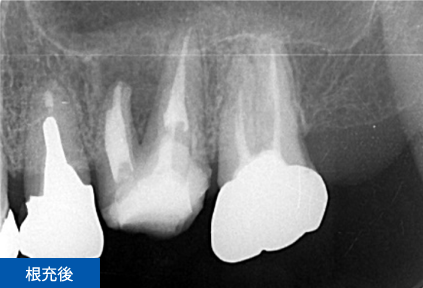

右下6番目の歯が、冷たいものがしみて痛いという主訴でご来院されました。